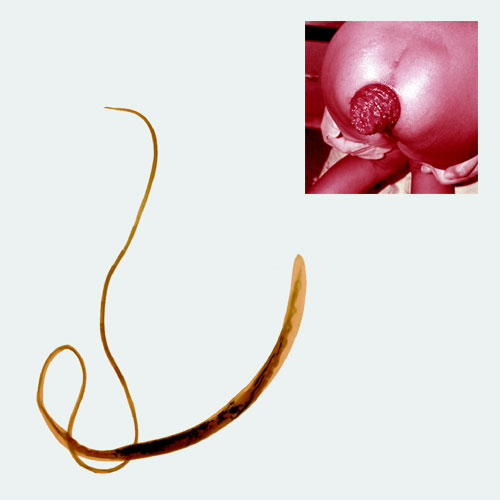

Trichuris trichiura, commonly known as a whipworm because it looks like a cow whip, grows up to about two inches (50 millimeters, or as long as a thumb). The most common way to catch whipworm is by ingesting dirt containing human feces that are loaded with its eggs (think: children playing in the dirt and then putting their fingers in their mouths). The whipworm, which sets up shop in the large intestine, is what Despommier says may be "the secret to curing Crohn's disease."

Patients with Crohn's disease—an autoimmune disorder in which the intestinal tract becomes chronically inflamed, leading to symptoms such as diarrhea, abdominal pain and rectal bleeding—are believed to have small proteins that resemble whipworm proteins jutting from the surfaces of their intestinal cells. Mistaking the protein protrusions for those of a whipworm, the immune system attacks them, causing Crohn's disease, Despommier explains. Studies have shown that when Crohn's patients are infected with whipworm, the body seems to redirect its focus away from its own cells and onto the worms, causing Crohn's symptoms to disappear. The problem with treating Crohn's disease with whipworm, of course, is that the worm causes its own suite of problems, including severe diarrhea, weight loss and anemia. Severe cases [see photo inset] can lead to rectal prolapse, a condition in which the walls of the rectum actually protrude from the anus.

Worldwide, some 800 million people, mostly children in tropical and subtropical climates, are infected with whipworm, according to the National Institute of Allergy and Infectious Diseases.